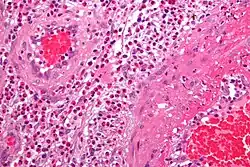

Micrograph showing a vasculitis (eosinophilic granulomatosis with polyangiitis). H&E stain.

• Some types of vasculitis display leukocytoclasis, which is vascular damage caused by nuclear debris from infiltrating neutrophils.[37] It typically presents as palpable purpura.[37] Conditions with leucocytoclasis mainly include hypersensitivity vasculitis (also called leukocytoclastic vasculitis) and cutaneous small-vessel vasculitis (also called cutaneous leukocytoclastic angiitis).